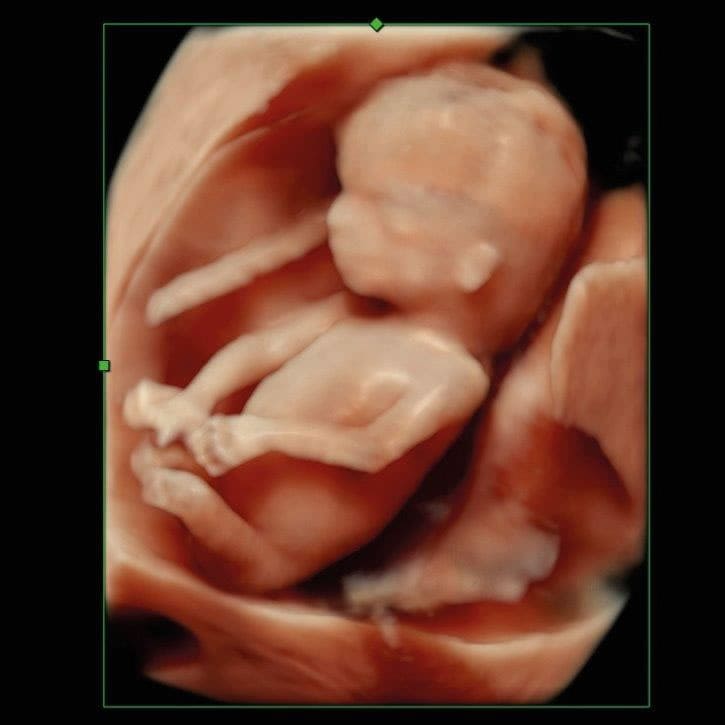

Im ersten Trimenon (1. Schwangerschaftsdrittel) bieten wir Ihnen verschiedene Untersuchungen an. Ab der 12. SSW können unter anderem bereits Kopf, Herz und Extremitäten untersucht und einige Fehlbildungen ausgeschlossen werden.

Im Ersttrimesterscreening (12-14 SSW) können wir durch Messen der Nackentransparenz, Darstellung des Nasenbeins und weitere Parameter zusätzlich das Risiko für Chromosomenstörungen bei Ihrem Kind ermitteln.

Ultraschall Ersttrimester Screening